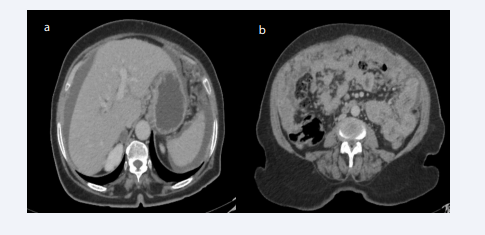

Faced with this clinical picture, an abdominal CT scan with injection of the contrast medium was performed objectifying multiple intraperitoneal tissue nodules in cake above and under mesocolic associated with an effusion of medium abundance with hepatic and splenic impressions achieving an appearance suggestive of peritoneal carcinomatosis (Figures 1-3).

a). Perihepatic and perisplenic effusion of medium abundance.  b). Nodular peritoneal thickening with epiploic cake suggestive of peritoneal carcinomatosis

Figure 1: a). Perihepatic and perisplenic effusion of medium abundance.

b). Nodular peritoneal thickening with epiploic cake suggestive of peritoneal carcinomatosis